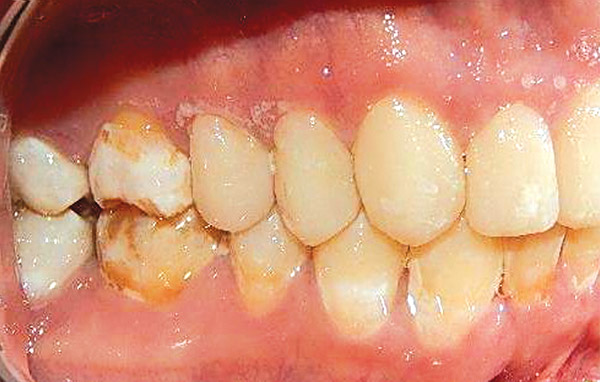

En las fotografías intraorales se muestra la fluorosis dental Tf4 y Tf7, las relaciones molares clase II molar y canina bilateral (Figura 3 y 4), el apiñamiento severo superior e inferior, con el órgano dental 35 en infraoclusión. El overbite aumentado y las líneas medias dentales no son coincidentes (Figura 5), las formas de arco superior e inferior son cuadradas (Figura 6 y 7).

Figura 4. Izquierda.